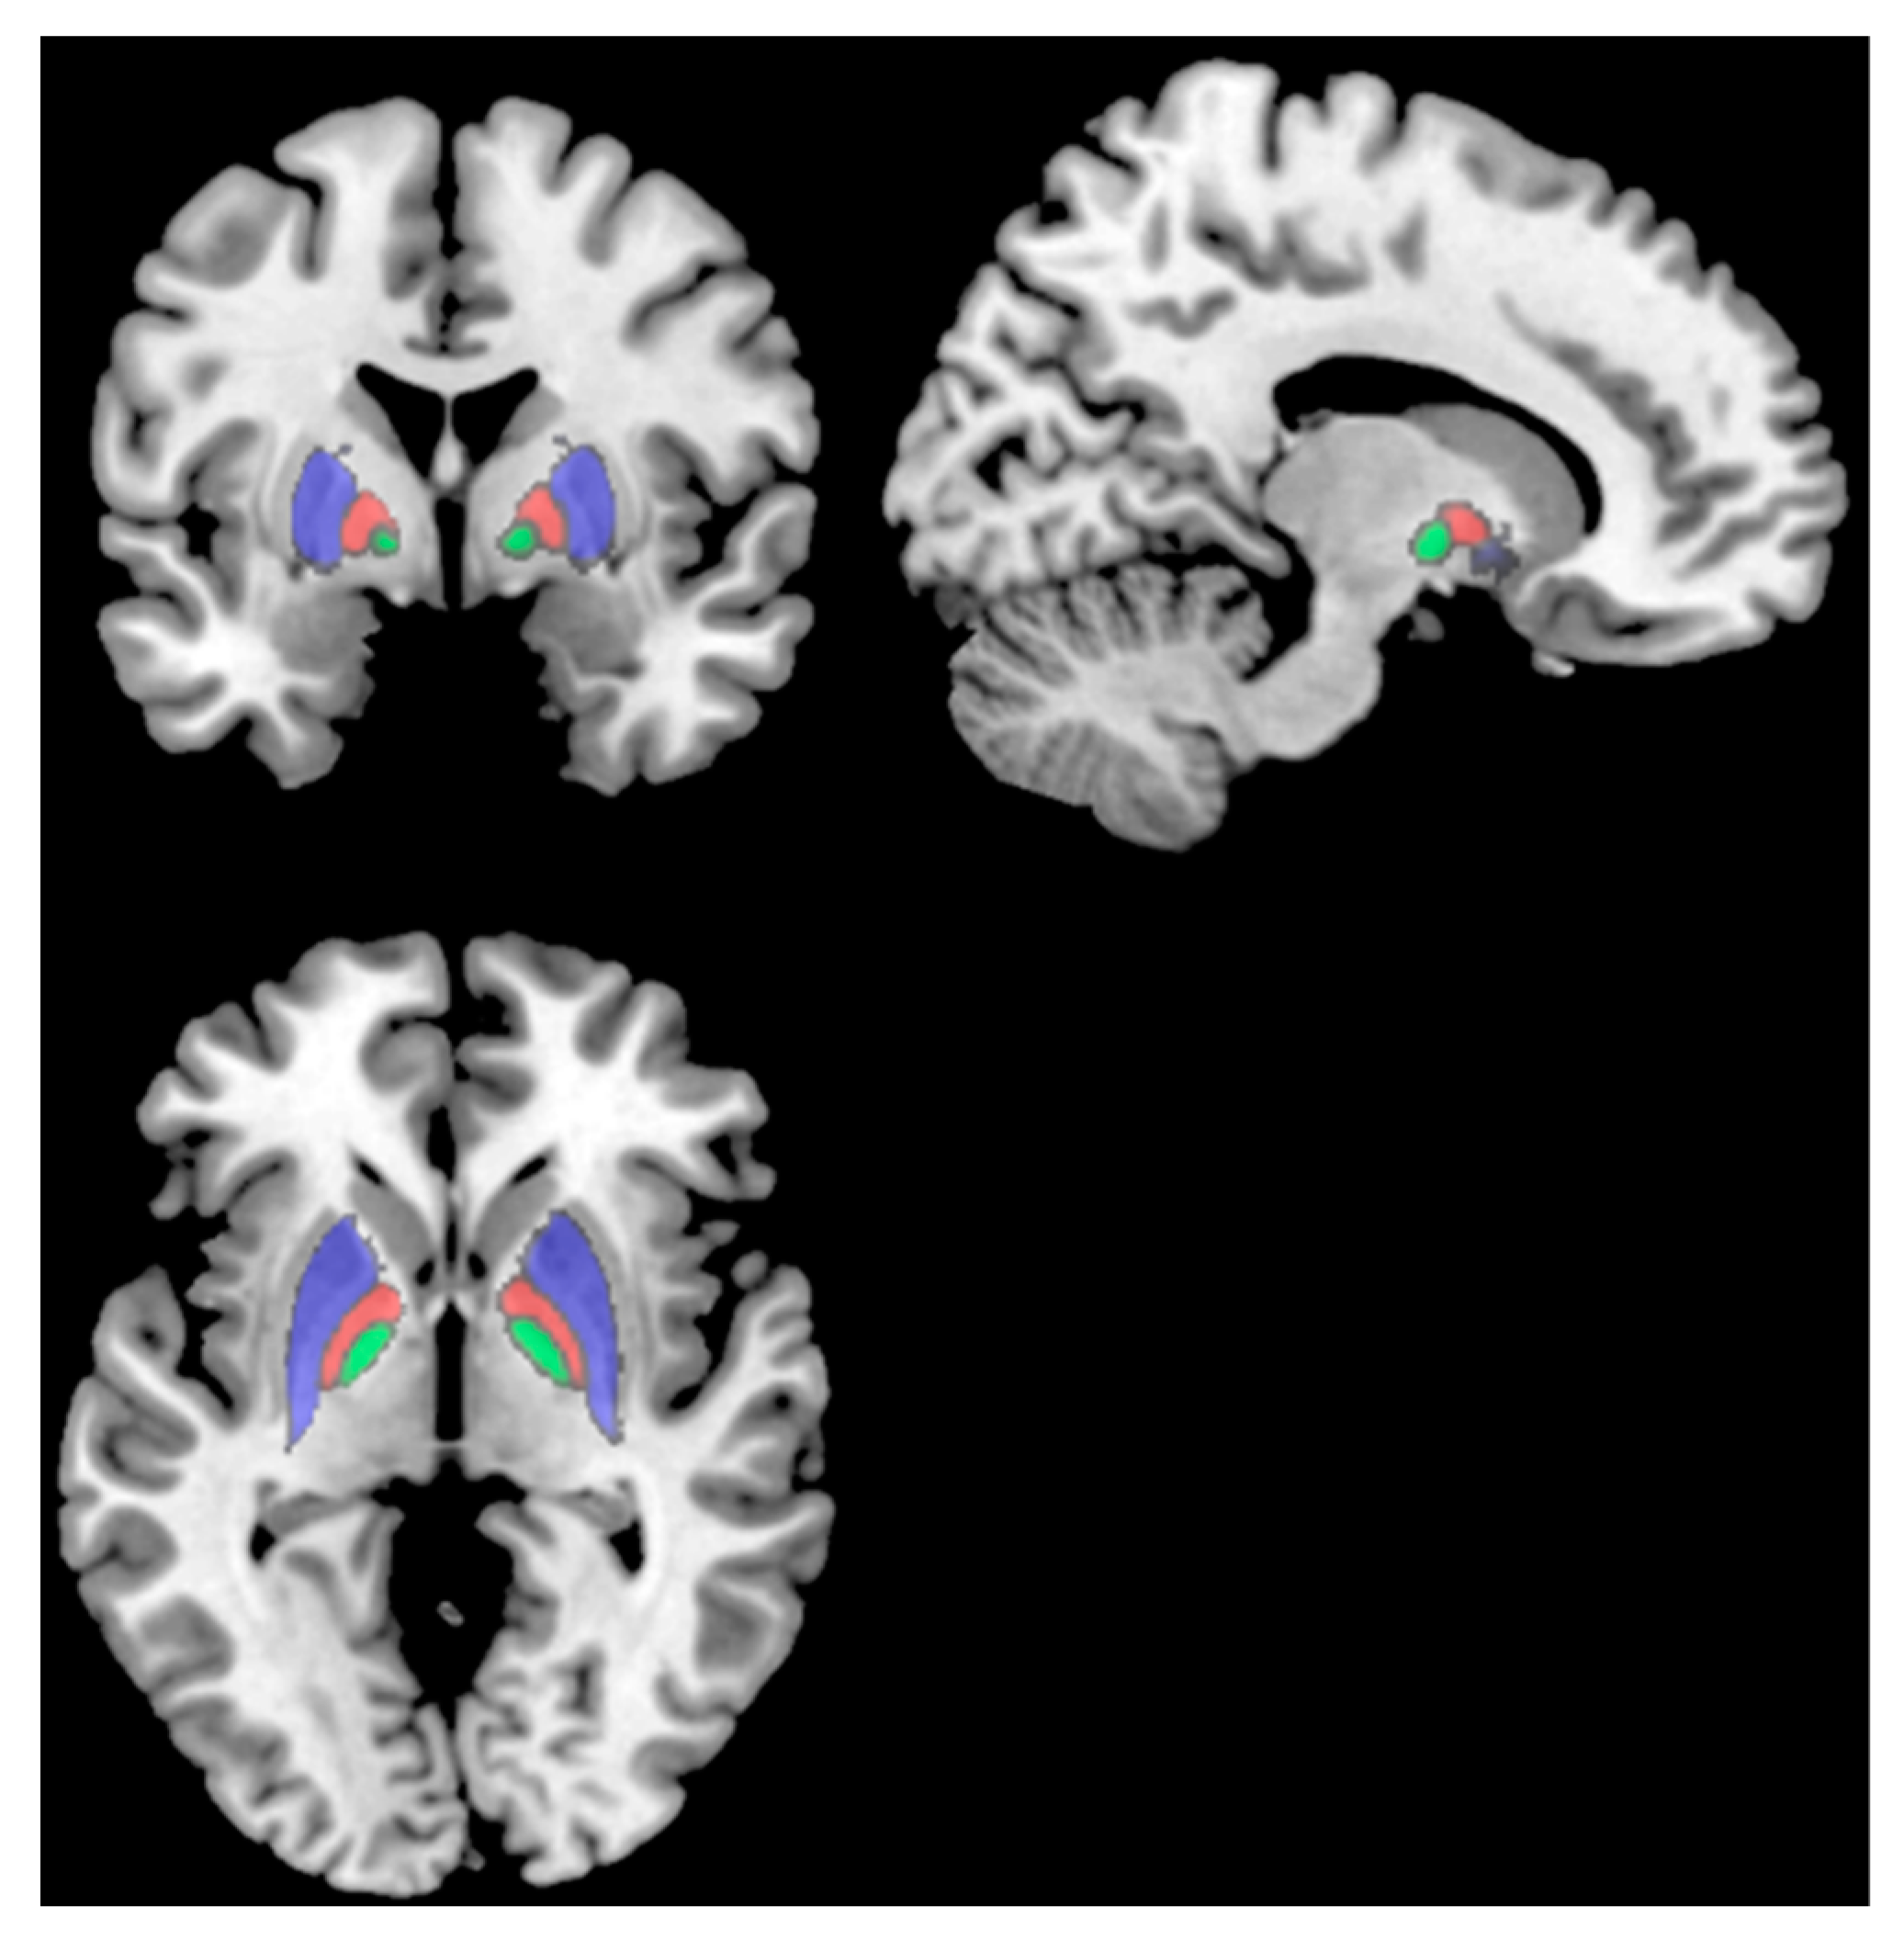

3.2. Structural Analysis

3.2.1. Relative Regional Volume Comparison: <6 Months Post-Infection vs. >6 Months Post-Infection

3.2.2. Relative Regional Volume Comparison: Fatigued vs. Non-Fatigued in >6 Months Post-Infection Group

3.2.3. Relative Regional Volume Comparison: Fatigued vs. Non-Fatigued in <6 Months Post-Infection

| (a). Results of the RRV Comparison between the Two Time Points. | ||||||

|---|---|---|---|---|---|---|

| Region | <6 Months Post-Infection | >6 Months Post-Infection | p-Value | Cohen’s d | ||

| L Putamen | 0.41 ± 0.02 | 0.43 ± 0.02 | 0.01 | 1.00 | ||

| R Putamen | 0.40 ± 0.03 | 0.42 ± 0.02 | 0.03 | 0.77 | ||

| L Pallidum | 0.11 ± 0.008 | 0.12 ± 0.007 | 0.01 | 1.30 | ||

| R Pallidum | 0.11 ± 0.009 | 0.12 ± 0.007 | 0.003 | 1.23 | ||

| L Thalamus | 0.59 ± 0.04 | 0.62 ± 0.03 | 0.03 | 0.84 | ||

| R Thalamus | 0.57 ± 0.04 | 0.60 ± 0.03 | 0.01 | 0.84 | ||

| R Cuneus | 0.59 ± 0.05 | 0.55 ± 0.04 | 0.01 | 0.87 | ||